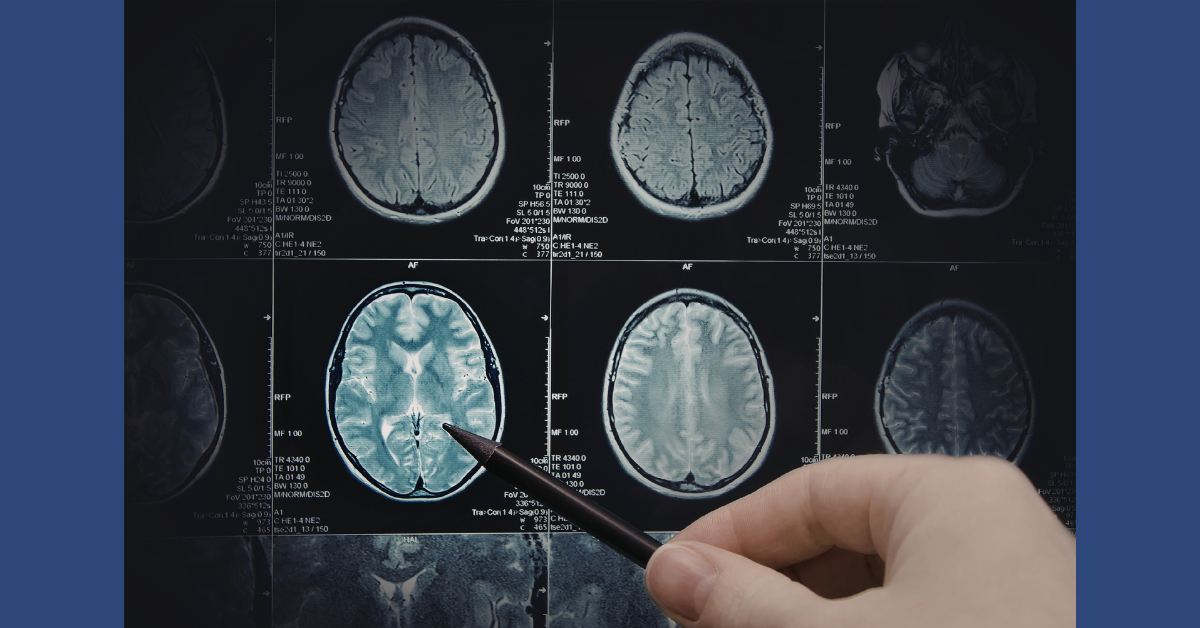

A concussion happens when the head or body is hit or shaken hard enough to cause the brain to move inside the skull. This movement can temporarily disrupt how the brain works, even if imaging tests appear normal. A concussion is considered a type of mild traumatic brain injury, often called mTBI.